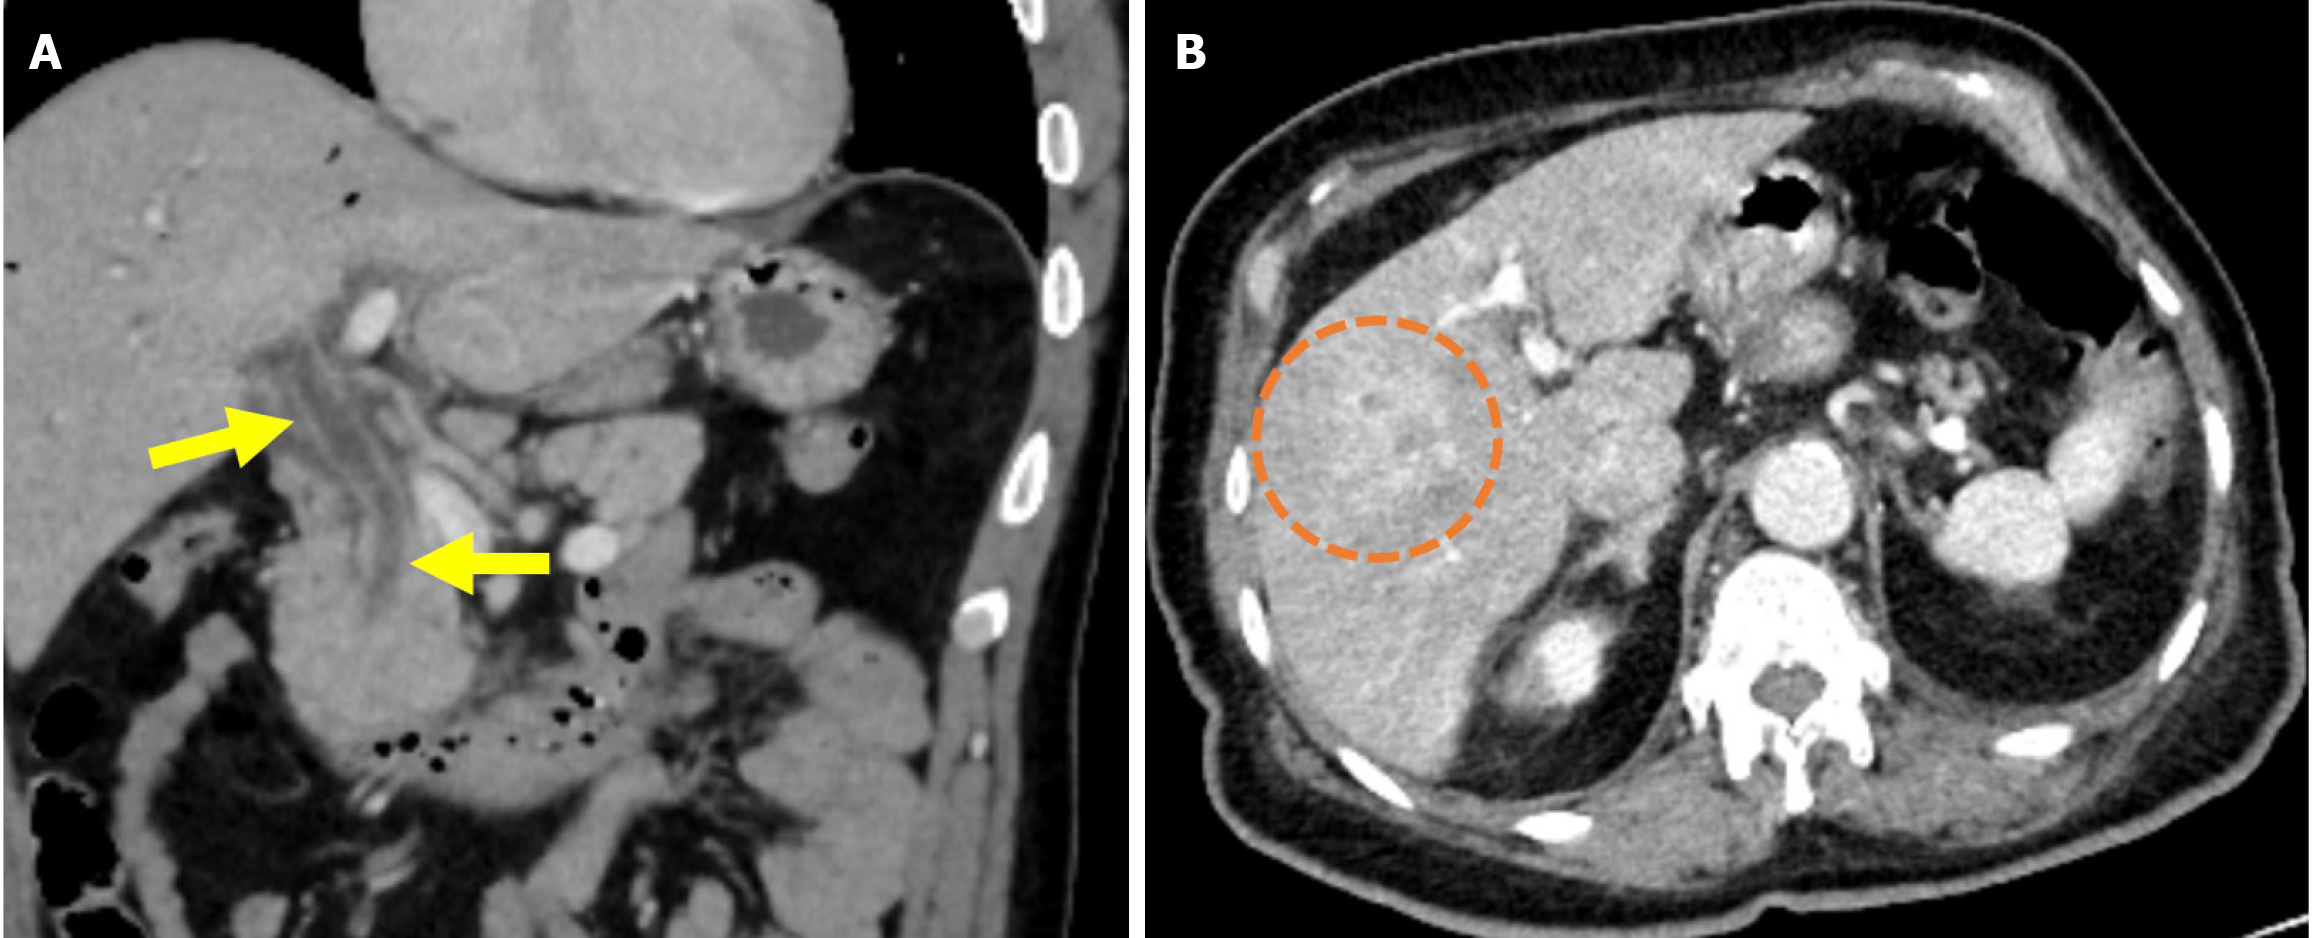

Distal migration of a biliary stent typically involves passage through the gastrointestinal tract without complication. However, there is the potential for perforation of the duodenum, jejunum, ileum, cecum, or colon[83]. Biliary stents cause perforation more frequently than pancreatic stents when migrating distally and may be related to the steeper exit angle of biliary stents into the duodenum[84]. These types of perforations are not included in the Stapfer classification nor other ERCP-related perforation systems. They present with pneumoperitoneum or retroperitoneal gas accumulation, fluid collections, or direct evidence of duodenal wall disruption on abdominal CT. While there are no specific guidelines for the management of stent-related perforations, imaging findings and the patient’s clinical status are critical for determining the appropriate intervention (i.e. surgical or endoscopic) (Figure 18)[79].

Figure 18

Figure 18  Distal stent migration and duodenal perforation. A and B: Coronal (A) and sagittal (B) contrast-enhanced computed tomography images in a 77-year-old female patient with a history of endoscopic retrograde cholangiopancreatography and biliary stenting for cholangitis, who presented with severe abdominal pain. Tachypnea and agitation were observed and were accompanied by nausea, fatigue, and impaired oral intake. Laboratory tests revealed elevated leukocyte counts, C-reactive protein levels, and lactate levels. The stent was found to have migrated distally into the duodenum and perforated the distal portion of the second part of the duodenum (yellow arrow). High attenuation-free fluid, suggestive of hemorrhage, was observed in the perihepatic region and mesentery (blue arrows). The liver exhibited heterogeneous contrast enhancement, consistent with impaired perfusion that was likely related to ischemia (orange circle). Emergent surgical intervention was required.